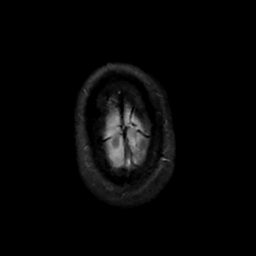

MR Study #14, June 2, 1991 -- Slice #47

[Home][Help][Clinical][Tour 1][Tour 2] Slice 47